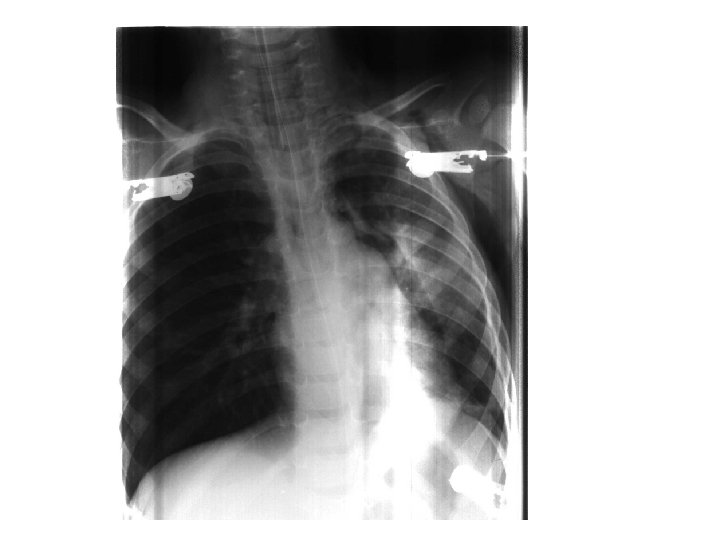

Case presentation • • • 2 year old boy from Delft Presents with tight chest and wheezing No previous episodes No TB contact No allergies No important previous medical history Cyanotic No clubbing Severely distress

Respiratory system • • Tachypnea Retraction Trachea central Reduced ventilation bilaterally but right more than left • Wheezing

Treatment • • • Berotec and Atrovent nebs Salbutamol IV Solumedrol IV Desaturated and intubated At this stage very little ventilation right and hyperresonant on percussion

Chest X-ray in severe asthma • Relevant in search for underlining complications – Pneumonia – Air leakages – Collapse • Ventilated patients